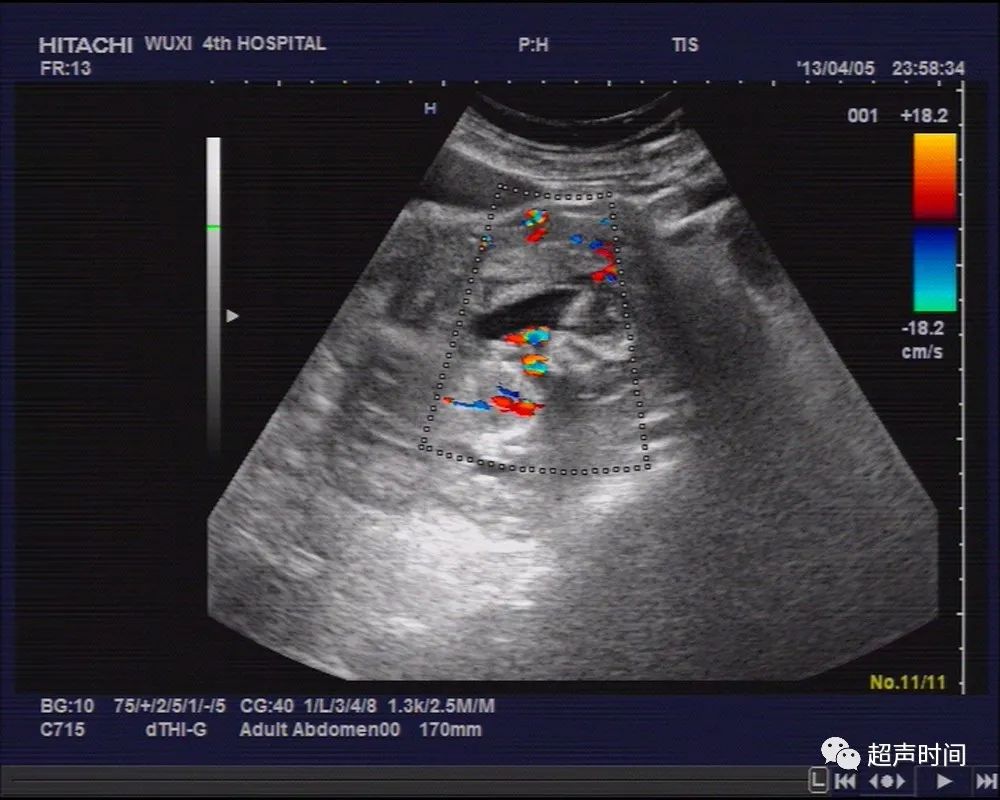

膀胱充盈可,子宫前位,稍大,肌层回声尚均,宫腔内未见明显孕囊结构,宫腔内可见低回声区,双卵巢显示不清,于左侧盆腔探及一类似妊娠囊结构,周边回声稍增强,其内可见一胎儿回声,头臀长约 71mm ,可见胎心、胎动(图 1~ 2 )。

图 2 胎儿可见胎心、胎动